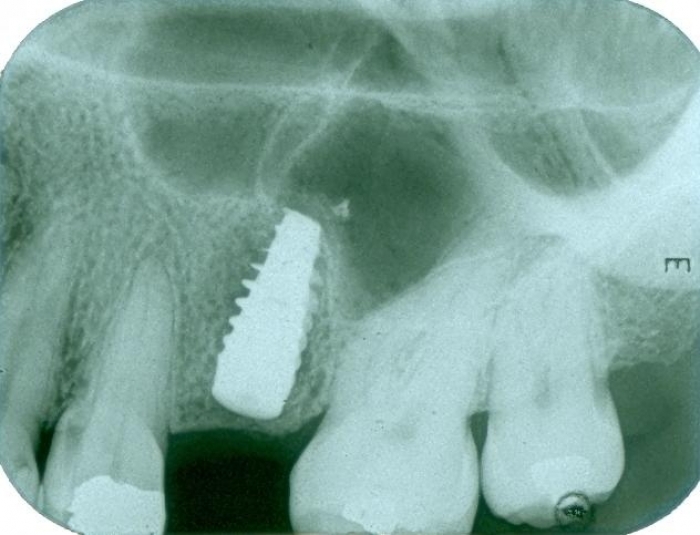

Raio X final

Dentes individuais em porcelana